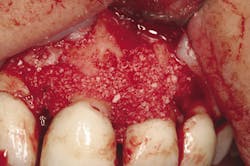

Retention of periodontally compromised teeth with initial, surgical, and supportive therapy has been shown to have high long-term success rates in the literature.3,4 Typical periodontal treatment for patients with moderate to advanced disease when first presenting to a dental office can consist of quadrant scaling and root planing, osseous surgery with or without regenerative therapy (Figs. 1 and 1a), and supportive periodontal maintenance at specific intervals. Estimated totals for this type of "start-up" treatment are in the range of $2,000 to $4,000 depending on geographic location (see Table A). This treatment, if maintained by the patient with diligent home care, has proven to be effective in terms of the prevention of further periodontal progression and tooth retention over a long-term period.5